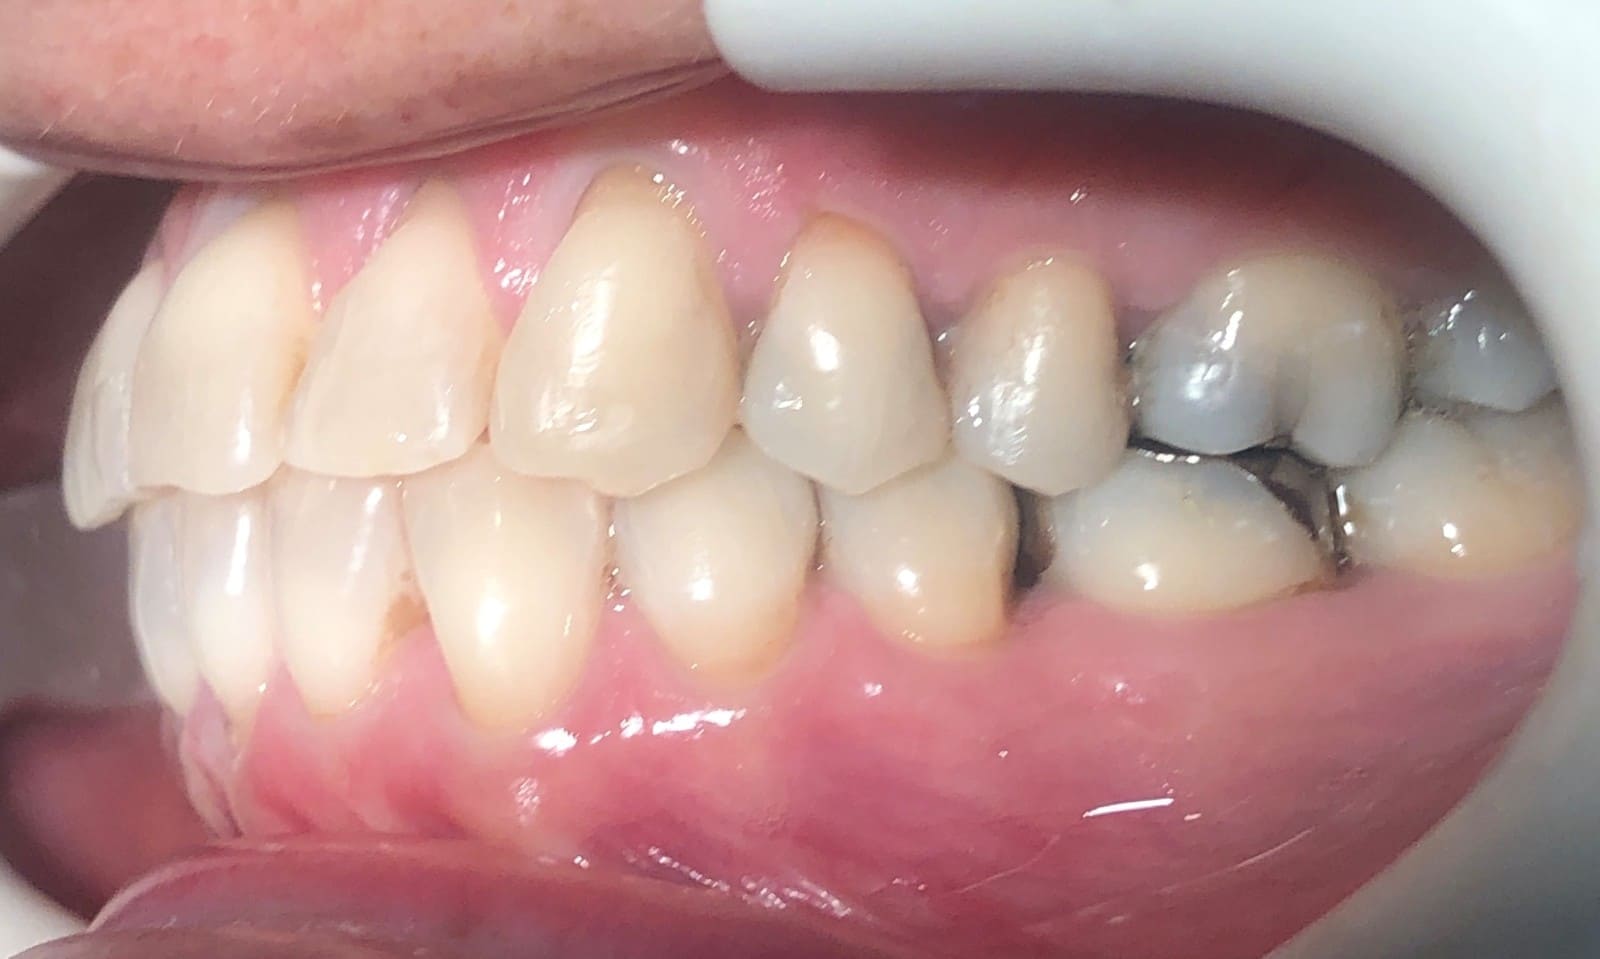

Initial

Final

- Class I relationship achieved

- Functional canine guidance on both sides

- Anterior crossbite corrected

- Normal overjet and overbite achieved

- Midlines coincident

- Proper axial inclination of incisors

- Curve of Spee leveled

- Arches aligned and coordinated

- Arch form improved

- Aesthetic smile line was achieved

- All treatment goals were achieved case